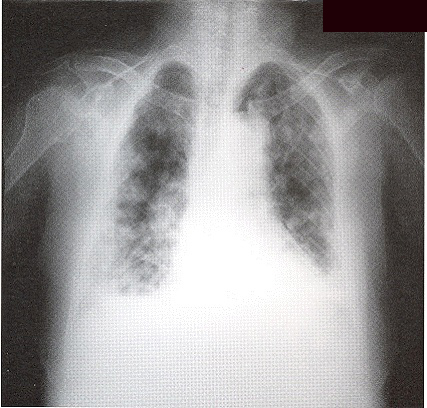

Complete blood picture showed mild neutrophilia. ESR was raised to 123mm/hr. She had mild renal impairment. Arterial blood gas on room air was nonnal on admission. Albumin/globulin ratio was reversed. Liver profile was normal. Sputum for culture grew oral flora and all smears for acid-fast bacilli were negative. CXR (Fig I) showed bilateral patchy opacity with nonnallung volume. No abnonnal mediastinal shadow was found. Old CXR of this patient was nonnal (Fig 2).

Initially, she was treated as community acquired pneumonia. However her symptom did not improve and she got persistent low-grade fever. CXR showed even more extensive shadow. Bronchoscopy was performed but no endobronchial lesion was found. Transbronchial biopsy was taken from left lingular lobe showed non-specific inflammation. Neither malignant cell nor acid-fast bacilli was found. CT thorax (Fig 3 & 4) was performed which showed widespread ill-defined patchy and nodular opacities and small reactive mediastinal lymph node. CT guided fine-needle aspiration of lung opacity was perfonned but material obtained was insufficient for diagnosis. Her general condition deteriorated despite multiple course of antibiotics treatment. She developed type 1 respiratory failure with oxygen dependency. Open lung biopsy was arranged but was withheld due to poor respiratory reserve. Another session of bronchoscopy was performed. This time the transbronchial biopsy showed evidence of diffuse alveolar damage. Her condition deteriorated further and became bed-ridden. On further questioning, amiodarone has been taken by patient for cardiac problem for few years and was stopped few months prior this admission due to bradycardia. Amiodarone pulmonary toxicity was suspected and oral prednisolone with a dose of Img/kg/day was started.